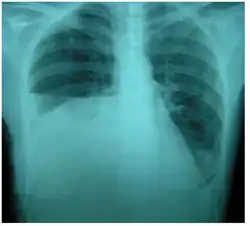

| Right sided pleural effusion caused by urinothorax | |